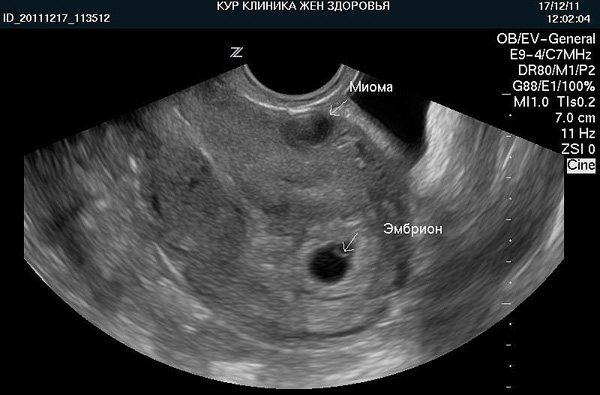

Фото 1. Как выглядит миома матки на УЗИ.

На снимке хорошо видна интрамуральная миома и эмбрион. Предполагаемый срок беременности – 5-6 недель. Миома не выходит в полость матки и на данном этапе не мешает развитию плода:

Фото 2. Заключение. Расшифровка.